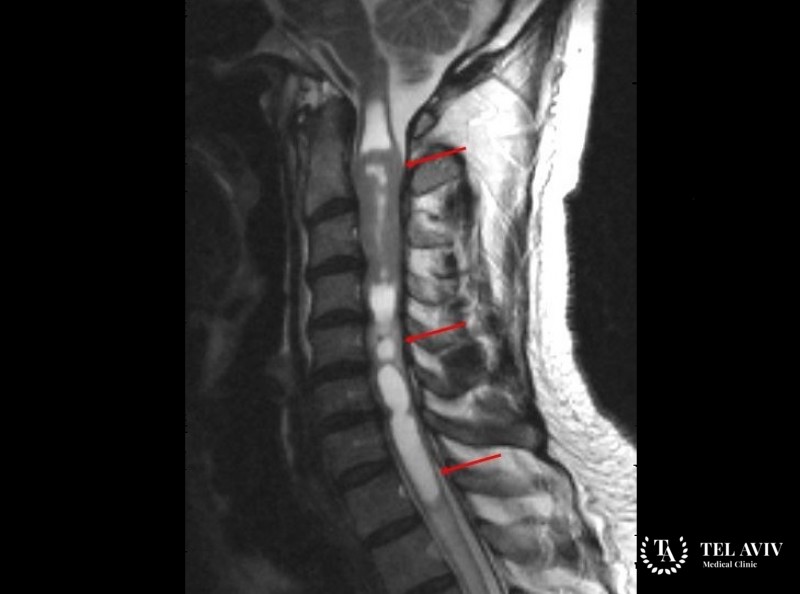

Для диагностики проводится первичная пальпация, осмотр, опрос пациента. На базе подученных данных формируется план обследования. Эффективными диагностическими методами признают:

- Магнитный резонанс;